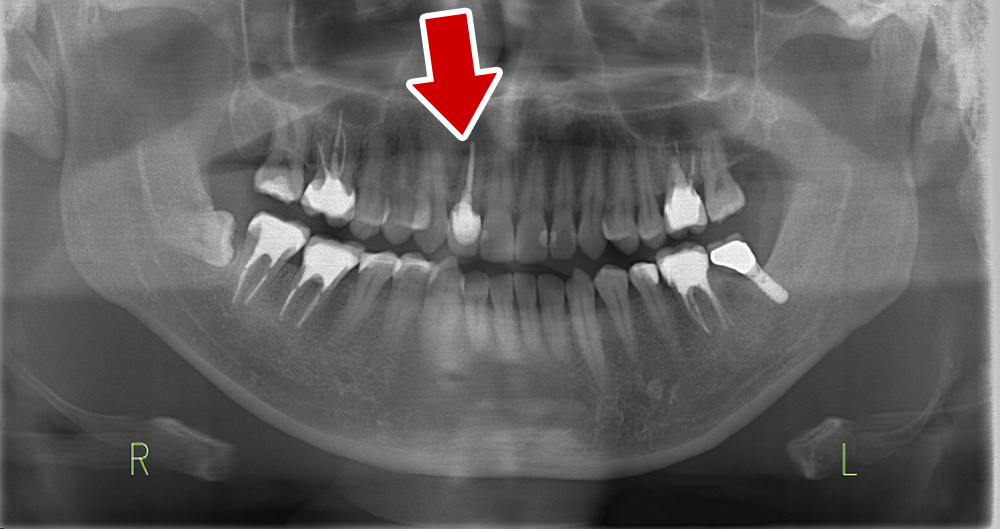

STEP2 施術前の検査

顎の骨に人工物を埋め込むため、神経や血管の位置、骨の厚みや強度などを精密に確認します。インプラントを安全に支えられる条件を満たしているかを事前に把握します。

歯科用CTや3Dスキャナー(iTero)で精密に検査し、コンピューターガイド手術を用いてより正確なインプラント埋入を目指します。